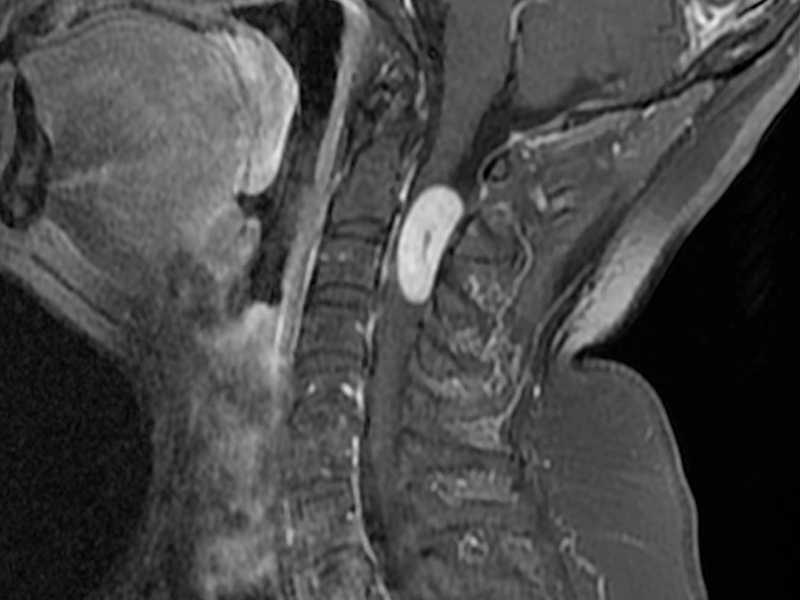

Boyun MR, ya da tıbbi adıyla servikal MR, boyun bölgesinin manyetik rezonans görüntüleme (MRG) tekniği kullanılarak ayrıntılı bir şekilde incelenmesidir. Bu yöntem, boyundaki kas, sinir, omurga ve disk yapılarını net bir şekilde gösterir.

Servikal MR, boyun bölgesindeki kemik, kas, sinir ve disk yapılarını detaylı bir şekilde incelemek için kullanılan ileri bir görüntüleme yöntemidir. Manyetik rezonans teknolojisiyle çalışan bu cihaz, güçlü manyetik alanlar ve radyo dalgaları yardımıyla vücudun iç yapısını görüntüler.

Boyun MR, boyun fıtığı, sinir sıkışması, tümörler, enfeksiyonlar, doğumsal anormallikler, omurilik hastalıkları ve travmatik yaralanmalar gibi durumların değerlendirilmesinde kullanılır. Ayrıca, baş ve boyun bölgesindeki damarsal problemleri, inflamatuar hastalıkları ve multipl skleroz gibi nörolojik hastalıkları teşhis etmek için de bu yöntem tercih edilir.

Servikal MR, özellikle boyun fıtığı, omurga daralması (spinal stenoz), omurilik ve sinir kökü tümörleri, multipl skleroz, disk dejenerasyonu ve travma sonrası yaralanmalar gibi hastalıkların teşhisinde kullanılır. Ayrıca, boyun bölgesindeki enfeksiyonlar, inflamasyonlar ve doğumsal anormallikler de bu yöntemle saptanabilir.